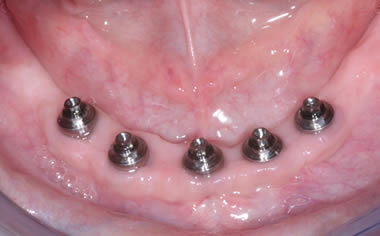

Case One (5 images)

Full set of lower teeth fixed onto five dental implants.

Case Two (8 images)